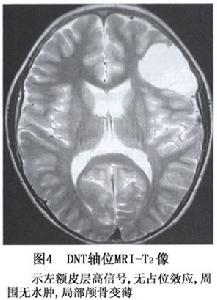

胚胎髮育不良性神經上皮腫瘤(DNT)是1993年WHO中樞神經系統腫瘤分類中新加入的一種神經元和神經膠質細胞來源的腫瘤,這是一種在對癲癇患者行癲癇灶切除後對其進行組織學檢查所發現的一種良性腫瘤1988年Daumas-Duport等首次報導了39例並對其進行了詳細討論,所有腫瘤均位於皮質內,由星形細胞、少枝膠質細胞和神經元構成。

DNT少見,自Daumas-Duport首批報導39例以來,以後均只有零星個例報導腫瘤多見於兒童,但也有青年患者,男女性無明顯差異。DNT好發於幕上,62%~78%位於顳葉,其餘幾乎均位於額葉。有人報導DNT占20歲以下組神經上皮性腫瘤的1.2%全年齡組的0.63%

胚胎髮育不良性神經上皮腫瘤位於皮質結節狀,瘤組織鬆散,瘤內部分為囊性。腫瘤由神經元、少突細胞和星形細胞構成,腫瘤周圍皮質有局灶性發育不良神經元排列紊亂,瘤周白質內可見移位神經細胞。在低級別的膠質瘤區域間分布有小神經元區及大神經節細胞區,從而形成多結節樣改變瘤內囊腔內含有酸性黏液。部分毛細血管周圍由膠質纖維形成鞘,四周繞有小而圓的少枝細胞其中有時可見有神經元。腫瘤內無壞死、血管內皮增生及瘤細胞核分裂。免疫組化染色可見瘤內細胞密集區MIB-1染色陽性,血管周膠質鞘GFAP陽性。

胚胎髮育不良性神經上皮腫瘤病程長,常在幼年或年輕時發病,主要表現為複雜性的局灶性癲癇發作。癲癇常為頑固性而不易控制。腦電圖常有病灶部位的癲癇波存在。因本病生長緩慢,局部顱骨可受壓變薄。

對於胚胎髮育不良性神經上皮腫瘤手術切除來消滅致病灶是有效方法,手術目的是切除病灶控制癲癇發作可作病灶全切除,或是對發育不良的皮質及部分病灶切除,一般術後癲癇能完全消失,不需術後放療或化療,

胚胎髮育不良性神經上皮腫瘤預後好,很少復發,不影響病人生存。